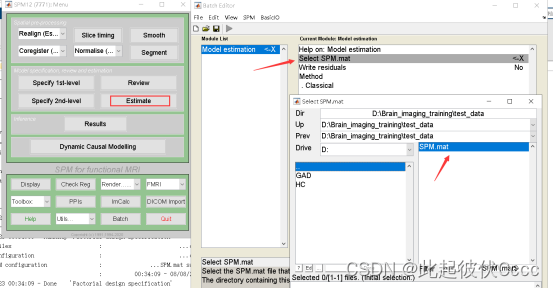

1.点击Estimate,选择上一步生成的SPM.mat文件,点击run运行